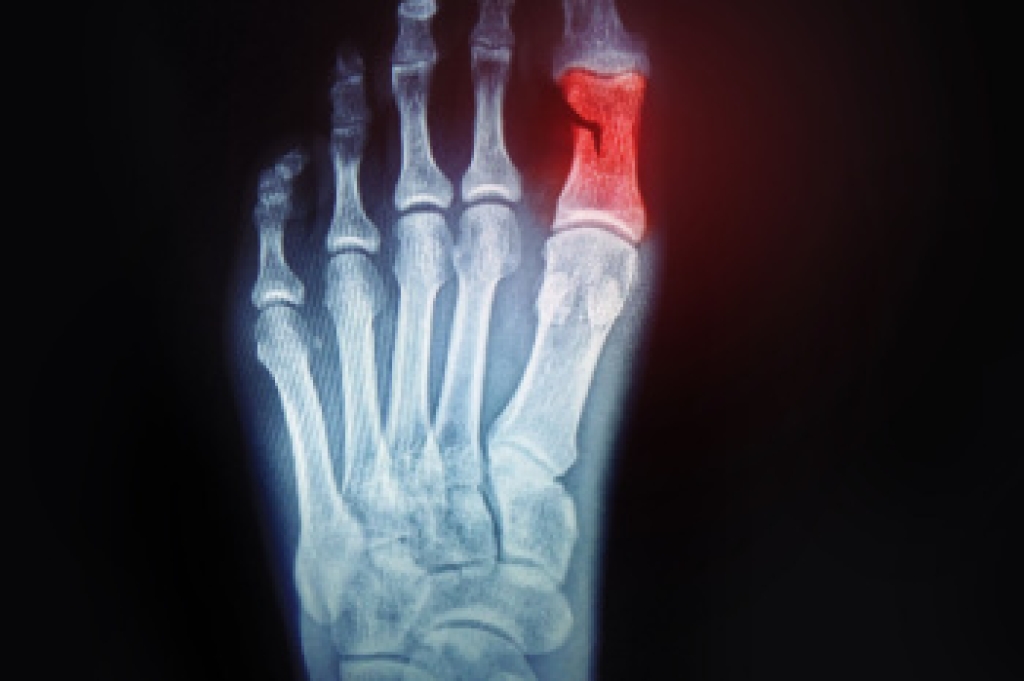

Plantar fasciitis is caused by inflammation of the plantar fascia, the thick band of tissue that supports the arch and connects the heel to the toes. It often leads to heel pain and stiffness, especially with first steps after rest. Risk factors include prolonged standing, repetitive strain, wearing poor footwear, flat feet, high arches, and excess body weight. Effective foot orthoses can help by supporting the arch, cushioning the heel, redistributing pressure, and reducing strain on the plantar fascia. A podiatrist can evaluate foot mechanics, confirm the diagnosis, and design custom foot orthoses as part of a comprehensive treatment plan. If heel pain is affecting comfort or mobility, it is suggested that you consult a podiatrist who can discuss the benefits of custom orthotics for relief and comfort.